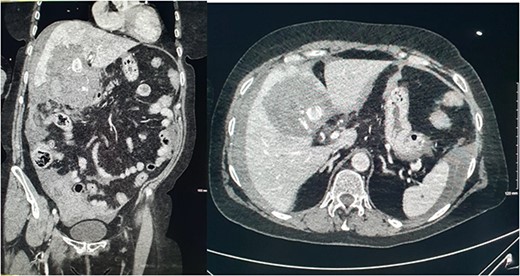

She presented on this occasion with right upper quadrant pain and collapse. Computed tomography (CT) abdomen and pelvis with intravenous contrast in the portal venous phase was performed, demonstrating perforated acute calculous cholecystitis and active haemorrhage (Fig. 1). At this point, Interventional Radiology and Upper gastrointestinal (GI) Surgery in our institution were contacted, and the patient was transferred for emergency embolization. The patient was haemodynamically unstable, so the massive transfusion protocol was commenced.

CT abdomen and pelvis with intravenous contrast in the portal venous phase was performed demonstrating perforated acute calculous cholecystitis and active haemorrhage.